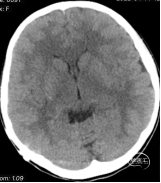

患儿,女性,9岁。因右侧脑室囊肿腹腔分流术后8年余,突发头晕、头痛,呈阵发性,疼痛剧烈,持续数十分钟后缓解。伴视物模糊、恶心、呕吐,就诊当地医院,查颅脑CT提示:右侧脑室囊肿引流术后,脑水肿,侧脑室变小(如下图):

行腰穿提示:>220mmH2O,予以“甘露醇”脱水处理,但上述症状仍未见好转,于2022年4月15日晚,急诊转入福建三博福能脑科医院。